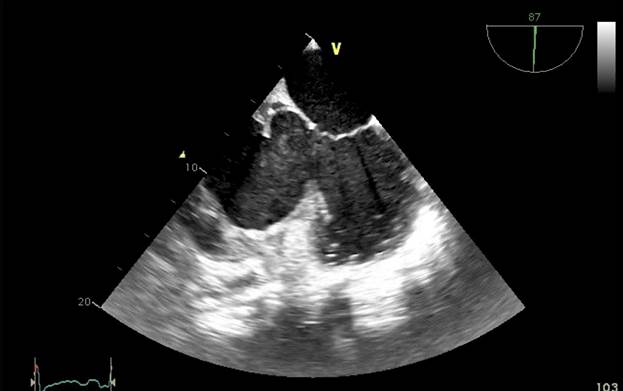

Aproximadamente 3 Semanas posterior al alta presenta cuadro de insuficiencia respiratoria asociado a insuficiencia cardiaca descompensada por lo que acude a nuestro Hospital de Especialidades Abel Gilbert Pontón siendo internada en Unidad Coronaria, a su ingreso se evidencia dolor precordial y torácico bilateral que irradia a región dorsal acompañado de disnea clase funcional NYHA IV/IV, tos persistente y edema leve de miembros inferiores, los laboratorios realizados evidencian anemia leve con hb 10.8 g/dL, péptido natriurético elevado de 12895 pg/ml, enzimas cardiacas negativas, hematuria y proteinuria en uroanálisis; en la radiografía de tórax se muestra cardiomegalia y derrame pleural bilateral; En electrocardiograma taquicardia sinusal, dextrorrotación, complejo QS en cara inferior, sin alteraciones de la onda T y segmento ST. En eco de pleura muestra derrame pleural derecho de moderada a gran cuantía y derrame pleural izquierdo moderado, sospechando de colagenopatía vs enfermedad autoinmune a descartar. Se realiza ecocardiograma transtorácico se evidencia formación aneurismática del VI de 9.5cm x 9.7cm tapizado por trombos con pérdida de la continuidad a nivel perimembranoso septal, además de una miocardiopatía dilatada con FEVI (fracción de eyección del ventrículo izquierdo) 28%. El estudio de líquido pericárdico da como resultado exudado con relación líquido/sérica de LDH 1,8 y proteína 0,7. En ecocardiograma transesofágico (Ilustración 1,2,3) se confirma pseudoaneurisma de gran tamaño del VI en región basal posterior con flujo bidireccional de 10 cm x 7,22cm tapizado de formación trombótica con pérdida de la continuidad de la región basal y posterior del VI con hipocinesia global e hipertensión pulmonar leve con insuficiencia mitral y tricuspidea leve por lo que se decide resolución quirúrgica.

Ilustración 1 Ecocardiograma Transesofágico. Pseudoaneurisma del VI en su porción septal

Fuente: Hospital de Especialidades Guayaquil “Doctor Abel Gilbert Pontón”.

Autor: Dra. María Sánchez Sánchez.

Se realizaron varios rastreos ecocardiográficos para determinar su estructura e incluso verificar su diagnóstico, para nuestro análisis es de gran relevancia el antecedente de la realización de la biopsia con ventana pericárdica. El pseudoaneurisma se encontraba muy posterior y basal comprometiendo al tabique interventricular sitio poco frecuente lo que causó grandes dudas de su afiliación fisiopatológica y del compromiso de ambos ventrículos. El eco transesofágico fue definitorio en este caso siendo una herramienta útil para el diagnóstico de pseudoaneurisma y análisis de secuelas quirúrgicas.